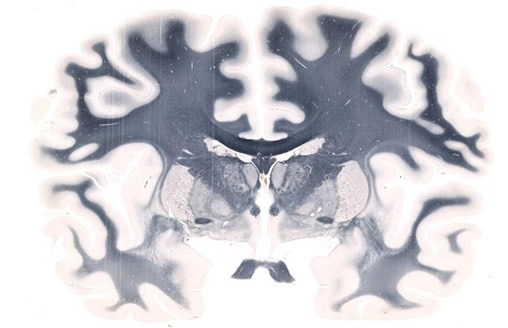

Whole-mount slide imaging enables innovative processes and outcomes in brain research. Since the TissueScope can accommodate slides of up to 6 x 8”, it is possible to scan an entire slice of the brain at once, allowing a precise 3D reconstruction of the whole brain to be created. In contrast to conventional microscopy, sections need not be excluded, meaning a global image is easier to obtain. To reconstruct a brain image from histology slides, the brain needs to be thinly sliced along one axis. Although thousands of slides require scanning, the TissueScope can image whole slides in just a few minutes. Furthermore, accessories such as the TissueSnap™ enhance throughput by offloading preview scanning and pre-processing, meaning the main scanner can operate at maximum speed and without interruption.

Figure 1. Whole-mount Brain scanned on a 5" x 7" slide at 20X resolution. Image credit: Huron Digital Pathology.

It is possible to use a tiling algorithm, so that for each brain slice, thousands of evenly spaced scans are captured at high resolution. The resolution achieved using the TissueScope, can reach up to 0.25μm at 40x magnification or resolution can be lower, at 0.50μm at 20x, or 1μm at 10x. This enables researchers to map the brain in detail, at a cellular level, and the potential to clarify uncertainties over observations made with lower resolution in-vivo imaging. Using suitable software, brain slice images can be compiled into a 3D volume. Hundreds of sections can be processed and viewed in just a few minutes, owing to the 3D histology software Huron offers that provides volumetric reconstruction of whole-mount slides. Furthermore, volumetric images from optical and confocal z-stacks can be read, visualized and investigated. Form there, scientists can proceed with cell counting, measuring the volume of specific regions and much more.